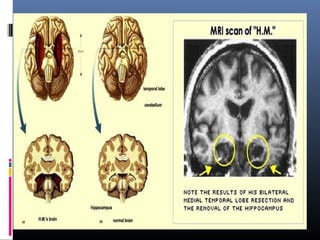

The Case of H. M., The Man Who Changed

the Study of Memory

Henry Molaison also known as H.M. – an

epileptic who had his temporal lobes

removed in 1953.

His seizures were

dramatically reduces- but so

was his memory

Mild retrograde amnesia and

severe anterograde amnesia

 Bilateral Medial Temporal Lobectomy

The removal of the medial

portions of both temporal

lobes, including most of the

hippocampus, and amygdala.